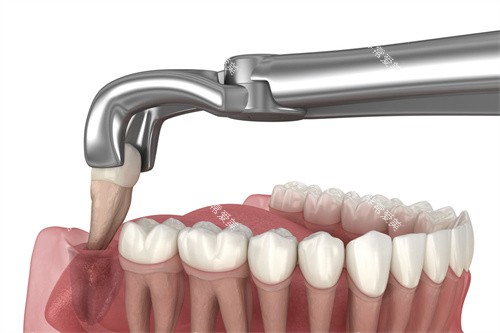

拔除时,医生不光需要小心翼翼地避免损伤邻牙和周围组织,还可能要通过切开牙龈、去除部分牙槽骨等操作来获得足够的操作空间,才能顺利将智齿取出。

不过,在经验充足、技术过关的口腔医生手中,即便面对复杂的横生智齿,也能凭借熟练的操作技巧和正规的设备,更大程度降低手术风险,维持手术顺利进行。